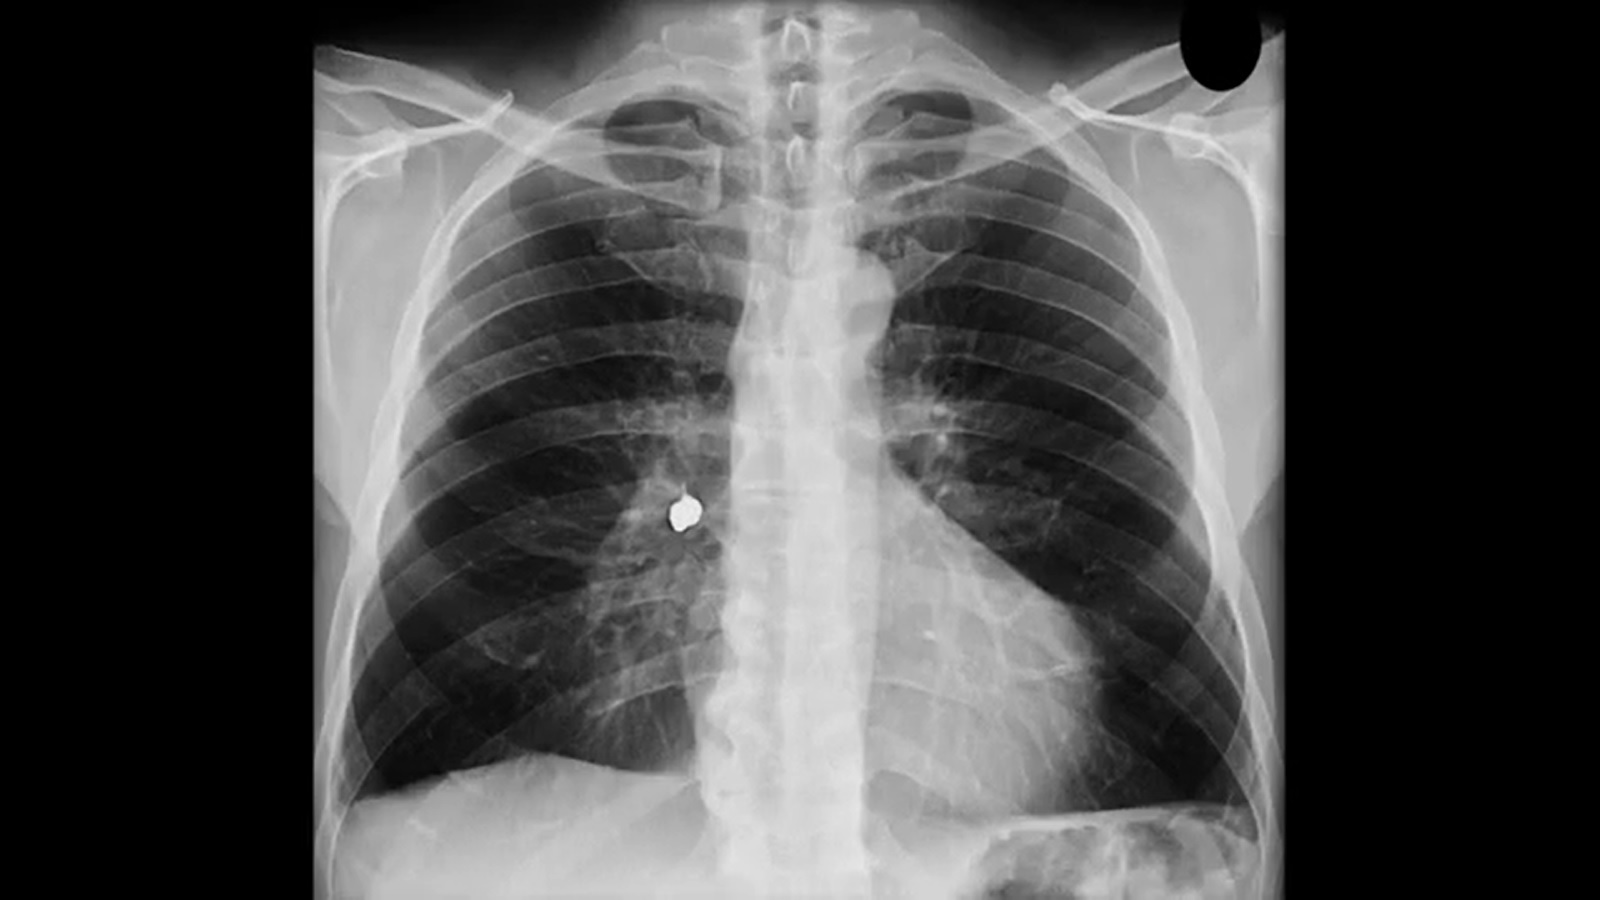

A identificação da broncoaspiração nas crianças, principalmente quando os pais não percebem, é algo desafiador e vai exigir do profissional de saúde expertise para solicitar exames de imagem que ajudarão no diagnóstico.

“O grande risco é quando o corpo estranho fica alojado no esôfago, local com mais sintomas e risco”, explica Giovana Tuccille Comes Brambilla, cirurgiã pediátrica do HCFMB. Segundo a especialista, o raio-x simples é o exame capaz de identificar a presença de um corpo estranho.